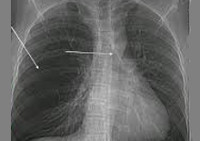

В качестве первичного скрининг-обследования всем пациентам проводится рентгенография легких. При этом на снимках обнаруживается повышенная воздушность пораженной доли, смещение средостения в здоровую сторону, уплощение купола диафрагмы. Расширенное обследование направлено на оценку тяжести анатомо-функциональных изменений в легких и выбор тактики лечения.